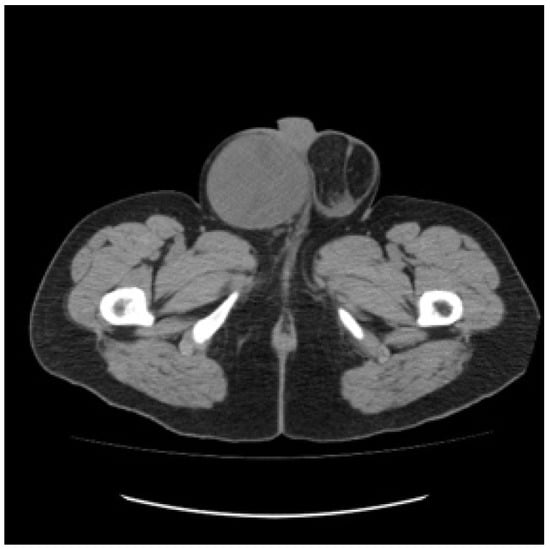

A 30-year-old patient awaiting a living-related donor renal transplant for chronic renal failure (creatinine 571 umol/L) related to reflux nephropathy presented to the local emergency room with right upper quadrant pain. Laboratory investigations revealed elevated liver function tests with hepatomegaly on abdominal ultrasound and multiple hepatic masses suspicious for metastasis. Subsequent computed tomography of the chest, abdomen, and pelvis confirmed multifocal hepatic lesions (Figure 1), periportal lymph nodes, a 4-mm nonspecific left lower lobe lung lesion, sclerotic lesions of the ribs, and a large mass in the left scrotum consistent with a testicular cancer (Figure 2). Bone scan also demonstrated sclerotic lesions in the seventh thoracic vertebrae, sternum, and the left iliac bone. Physical exam confirmed a large right testicular mass. His alpha fetal protein (AFP) was 62,777 umol/L (normal < 10), Beta-human chorionic gonadotropin (B-HCG) was 32 IU/L (normal < 1), and the lactic acid dehydrogenase (LDH) was 367 U/L (normal < 192).

Figure 2. Baseline unenhanced CT scan showing a large right scrotal mass.